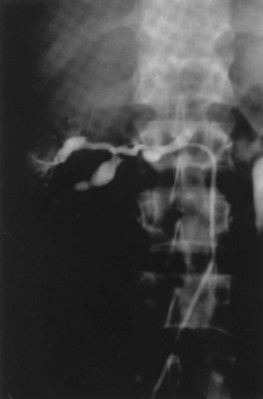

Primary intimal fibroplasia accounts for 10% of lesions and occurs in children and young adults. The process can develop in contralateral kidneys or other vessels in a progressive nature. Angiographically the disease has smooth, focal stenosis involving the proximal or middle portion of renal vessels or branches (Fig. 54–42).

Figure 54–42 Intimal fibroplasia.

(From Libertino JA. Reconstructive urologic surgery. 3rd ed. Philadelphia: Mosby; 1997.)